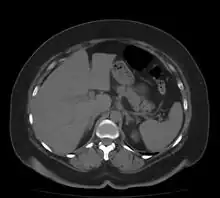

Bowel

Acute mesenteric ischemia

Both large and small bowel can be affected by ischemia. Ischemia of the large intestine may result in an inflammatory process known as ischemic colitis. Ischemia of the small bowel is called mesenteric ischemia.